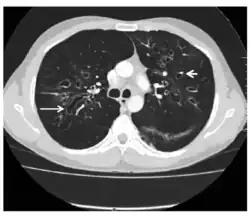

| Chest Xray of allergic bronchopulmonary aspergillosis showing left-sided perihilar opacity (blue arrow) along with non-homogeneous infiltrates (transient pulmonary infiltrates indicated by red arrows) in all zones of both lung fields | |